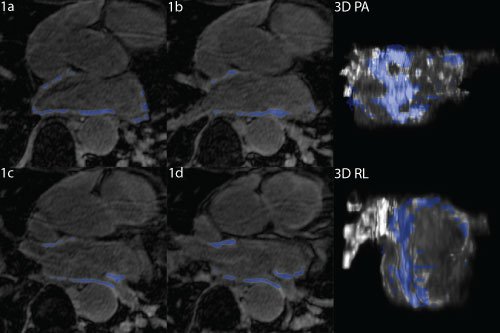

- Non-invasive (medical imaging) therapies combine with machine vision can help to quantify how effective a treatment has been and whether additional intervention is necessary.

Machine learning allows the building of patient specific models.

It can be difficult to apply new therapies because of how labor intensive it can be to create models outside of the research lab. Machine learning can be leveraged to segment images rapidly and efficiently without losing accuracy.

Structural changes in the heart correlate with electrical changes.

These structural changes aren't always reflected in the way the disease manifests; but strongly predict response to therapy. They are really hard to see without an invasive study, though. Medical imaging alongside computer vision, segmentation, and machine learning assessment can give insight to how far along the disease really is. This information then informs treatment options leading to better outcomes.

MRI combined with image processing pipelines provide a powerful tool to inform doctors how to treat arrhythmias. Visualizations can help providers plan intervention and then to communicate findings and care plans to the patient.

Creating positive feedback loops.

The resulting models provide key insights into how a patient will respond to treatment. Patients with more observed structural change and higher degree of scarring require much more aggressive therapy then those with less change. Over time, as more data is acquired, it is possible to even more effectively target therapy and predict outcome.